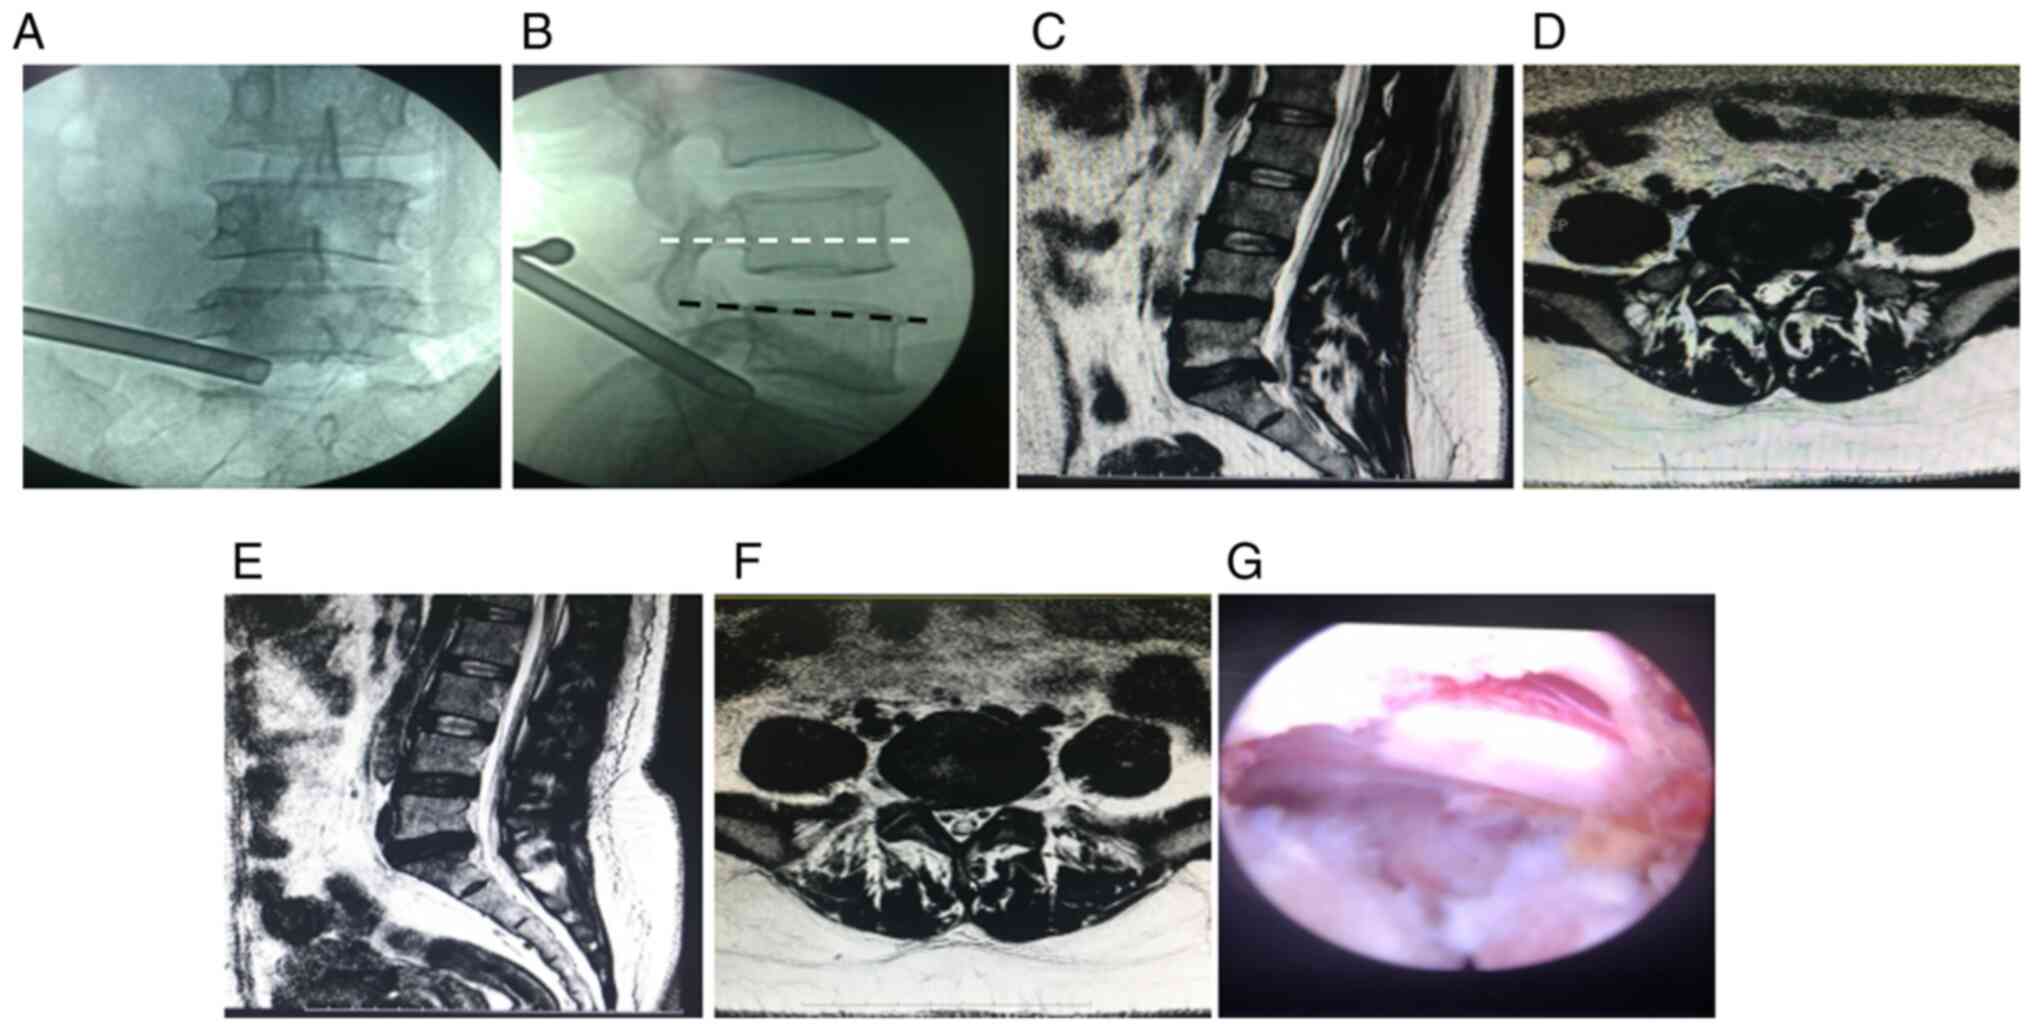

As shown in Table III, the differences in the duration of operation, amount of intraoperative bleeding and the VAS score and ODI of the lower back and lower limbs at each time point after the operation between group III and groups I and II were statistically significant (P<0.05), while those between group I and group II were not statistically significant (P>0.05). Intraoperative complications occurred in two patients with high iliac crest in group III. One had cerebrospinal fluid leakage due to a mild tear of the dura mater during the operation, which improved after symptomatic treatment. The same operation was repeated in another patient due to recurrence of disc herniation, after which the condition of this patient improved (Fig. 2).

Figure 2

Photographs before and after PETD for L5-S1 lumbar intervertebral disc herniation in a 45-year-old woman. (A) Intraoperative images of the working cannula in anteroposterior radiography of the lumbar. (B) Intraoperative images of the working cannula in lateral radiography of the lumbar. The upper edge of the L5 pedicle is shown in black, and the iliac crest is slightly below this line in this case. (C) Preoperative sagittal section of lumbar magnetic resonance imaging. (D) Preoperative transverse section of lumbar magnetic resonance imaging showing right-sided subaxillary herniation at the L5-S1 segments and a large herniated disc that compresses the dural sac and the right S1 nerve root. (E) Postoperative sagittal section of lumbar magnetic resonance imaging at 1 month after the operation. (F) Postoperative transverse section of lumbar magnetic resonance imaging at 1 month after the operation showing that the herniated L5-S1 disc has disappeared and that the dural sac and the S1 nerve root compression on the right side has been relieved. (G) The decompressed nerve roots can be seen after complete removal of the herniated disc tissue.